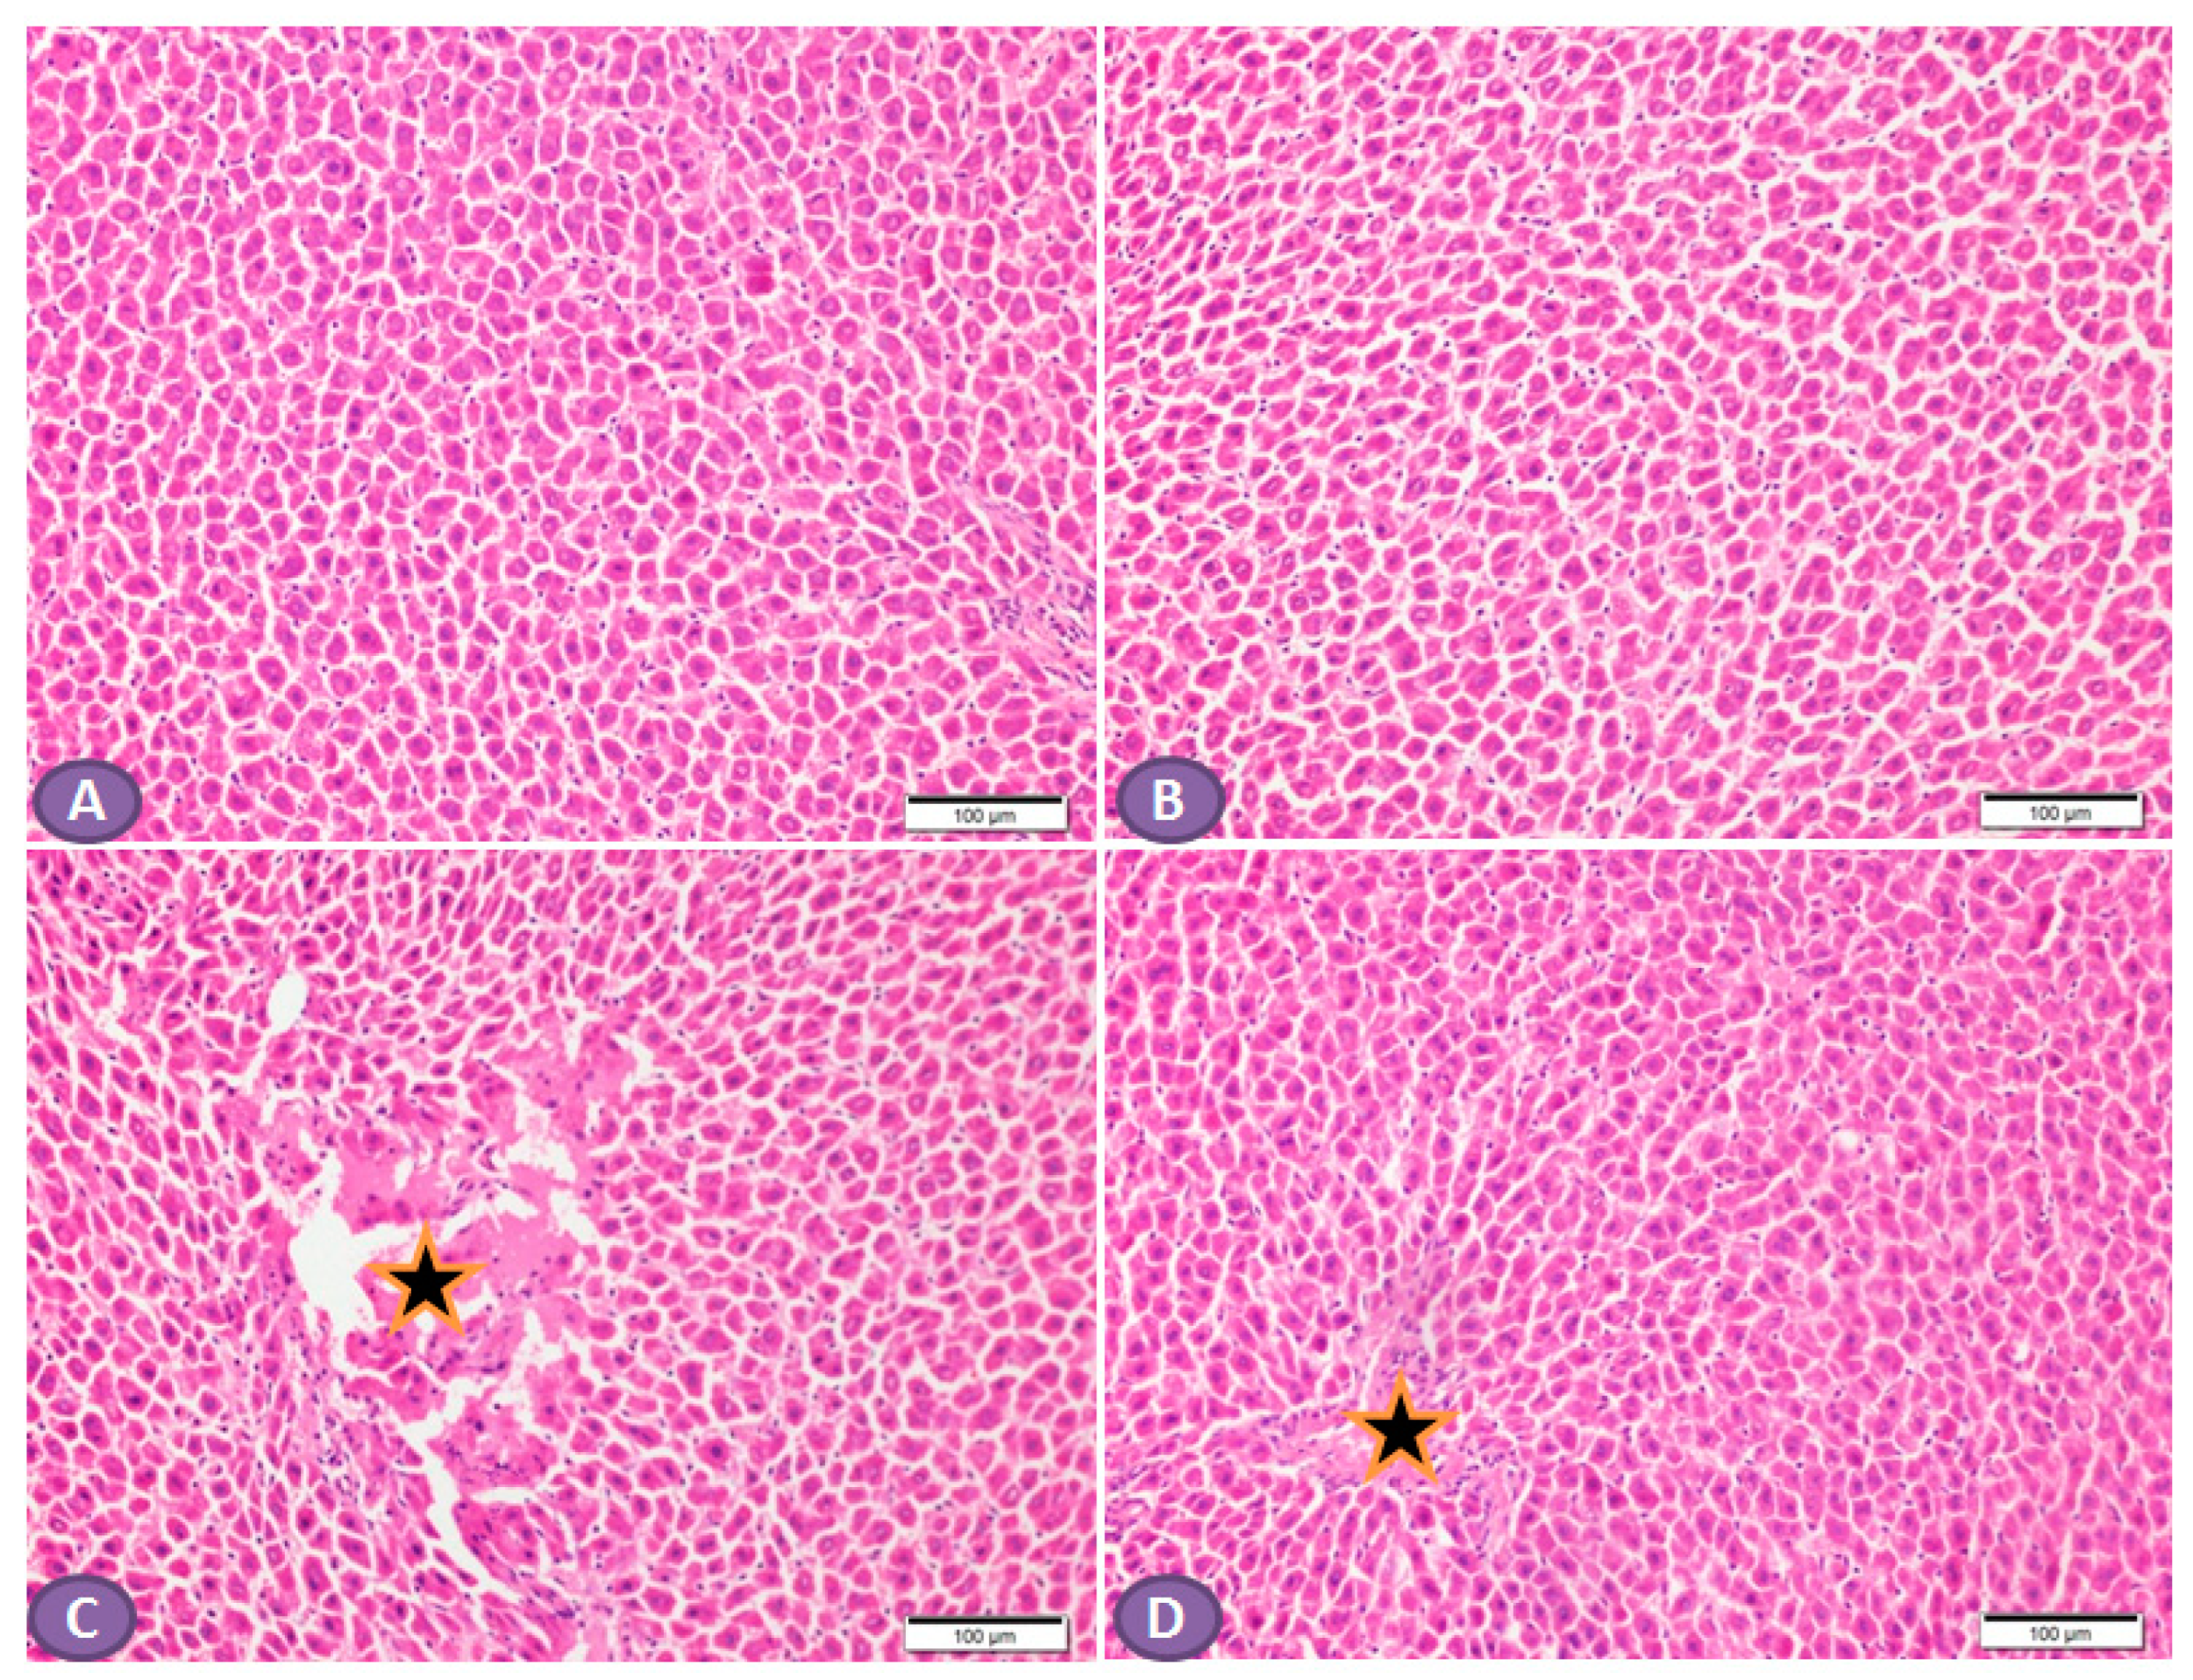

Histopathological examination of the H&E-stained liver sections of nondiabetic rats showed normal liver tissue with normal features of the architecture of hepatic lobules and portal tracts. (Figure 4A,B). Liver sections from diabetic rats revealed multiple patches of hepatic degeneration with the loss of a group of hepatocytes, inflammatory cellular infiltrations, and hepatocyte cytoplasmic degeneration (Figure 4C). On the other hand, sections from the liver of diabetic rats receiving ST showed a marked decrease in inflammatory cellular infiltrations; most of the hepatocytes were apparently with normal cytoplasm and nuclei (Figure 4D).

Figure 4.

Photomicrograph of H&E-stained liver section, scale bar = 100 µm. (A,B) represent normal nondiabetic control liver and liver of rat who received ST, respectively, showing normal histological architecture of hepatic lobules and portal tracts. Hepatocytes and the hepatic blood sinusoid are in normal state. (C) represents a liver section from rat receiving STZ as a model of diabetes, showing multiple patches of hepatic degeneration with loss of group of hepatocytes (star). The surrounding tissues show inflammatory cellular infiltrations and hepatocyte cytoplasmic degeneration. Some hepatocytes show nuclear pyknosis. (D) represents liver from diabetic rat who received ST, showing marked decrease in inflammatory cellular infiltrations; most hepatocytes are apparently within normal cytoplasm and nuclei. There is recovery of the hepatic lobular architecture. The degenerated patches decreased in number and size (star). ST, Sitagliptin; STZ, Streptozotocin.

In the scope of this study, the AST and ALT level was considered the initial indicator for liver injury [47]. The results revealed the release of liver enzymes such as ALT and AST, which were increased in T2DM rats compared to the normal control group and reduced with ST treatment. ST has a protective effect on the liver, manifested as an improvement in liver transaminases [48]. These results were supported by histopathological examination findings, which disclosed marked hepatic injury in the T2DM group. The biochemical and histological alterations associated with STZ induction were significantly decreased by ST treatment, indicating that ST could effectively counteract DM-induced liver cell injury.